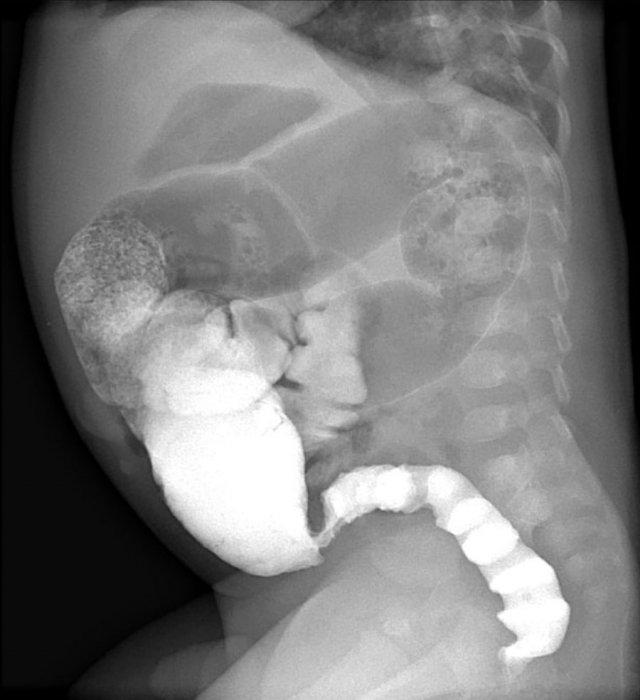

Các dấu hiệu bao gồm:

- Nhiều quai ruột non giãn cho thấy tắc nghẽn đoạn thấp

- Thụt tháo cản quang cho thấy khẩu kính nhỏ ở trực tràng, đại tràng sigma và đại tràng xuống

Chẩn đoán:

Bệnh Hirschsprung đoạn dài